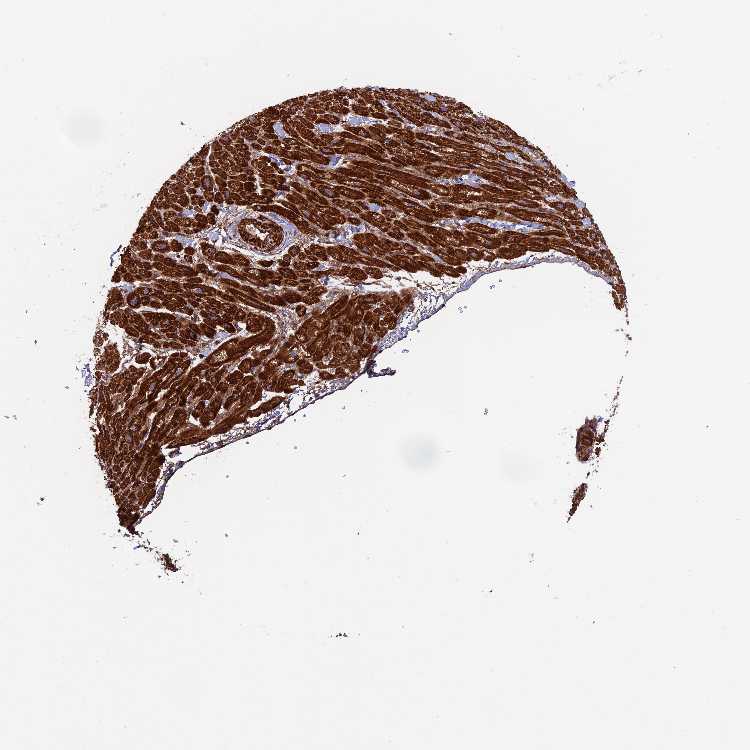

HEART MUSCLE - Antibody stainingi

Antibody staining in the annotated cell types in the current human tissue is reported as not detected, low, medium, or high, based on conventional immunohistochemistry profiling in selected tissues. This score is based on the combination of the staining intensity and fraction of stained cells.

Each image is clickable and will lead to virtual microscopy that enables deeper exploration of all samples and also displays staining intensity scores, fraction scores and subcellular localization as well as patient and tissue information for each sample.

Antibody HPA039708Antibody HPA040038

Cardiomyocytes MediumHigh